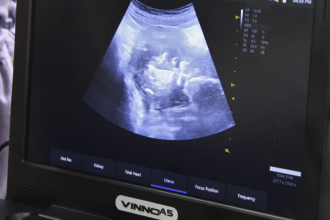

Умайн хоргүй хавдрыг түлэх мэс заслын эмчилгээг амжилттай хийжээ

"Амгалан амаржих газар" төрөлжсөн мэргэшлийн эмнэлэг /ААГТМЭ/-ийн эмч мэргэжилтнүүд энэ сарын 14-нд умайн хавдартай хоёр өвчтөнд хэт авиан хяналтан дор…